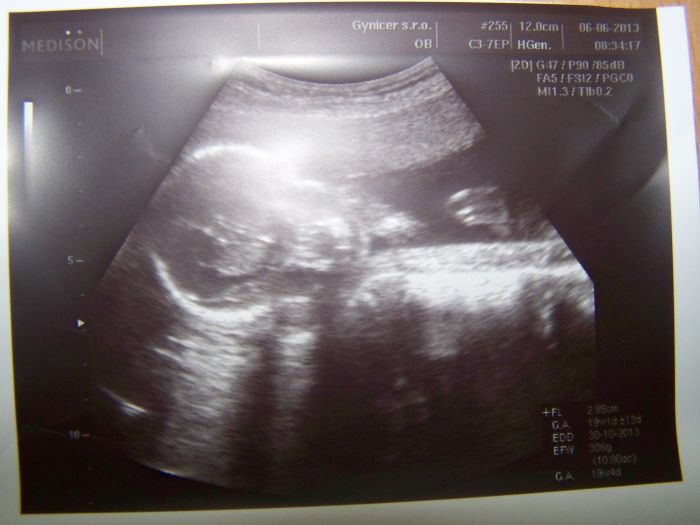

podávám hlášeníčko ze čtvrteční poradny ve 20tt. Takže nahoře mám zatím 2kg, což je super. No a dle UTZ vše v pořádku, miminko odpovídá, váží už 306g a je aktivní až až, kopká přesně od 18+3. A podle dr je to na 80% holčička, takže se nám splní sen a budeme mít páreček. V pondělí jdu na velký UT, tak už se mooc těším, Další kontrolu máme u mojí dr 4.7.